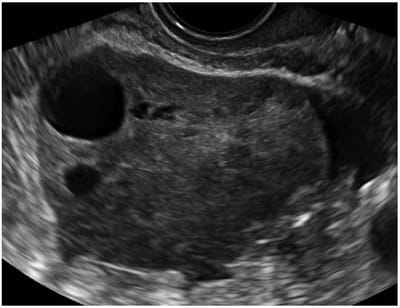

Quistes ováricos

Los quistes ováricos son una afección común en las mujeres durante la edad fértil. Se producen cuando se forma un quiste en el ovario. Un quiste ovárico puede causar síntomas o no. La mayoría de los quistes ováricos desaparecen sin tratamiento. En algunos casos, puede ser necesaria una cirugía para extirpar quistes grandes o en curso.

Síndrome de ovario poliquístico (SOP)

El síndrome de ovario poliquístico es un tipo común de trastorno hormonal. Causa agrandamiento de los ovarios que contienen numerosos quistes. La enfermedad de ovario poliquístico también puede provocar infertilidad, crecimiento excesivo de cabello y períodos abundantes, irregulares o ausentes. Si no se trata de manera adecuada, también puede aumentar el riesgo de contraer diabetes mellitus o cáncer de endometrio. Afecta de manera desproporcionada a las mujeres de color más que a otras mujeres. Los tratamientos incluyen medicamentos y reducción de peso.